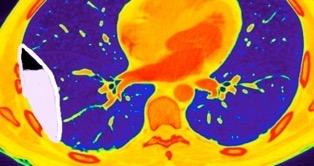

Makis W et al. Spectrum of Malignant Pleural and Pericardial Disease on FDG PET/CT. AJR. 2012